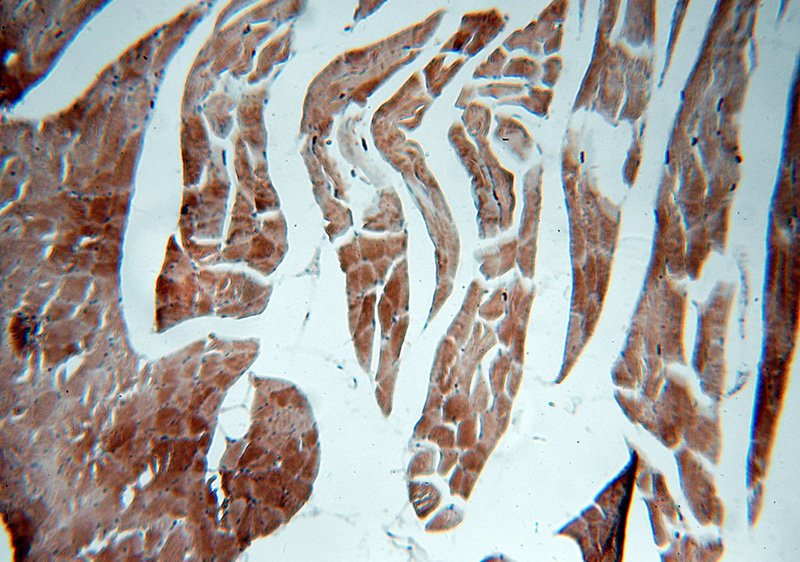

Immunohistochemical of paraffin-embedded human skeletal muscle using Catalog No:113089(NEB-Specific antibody) at dilution of 1:50 (under 10x lens)